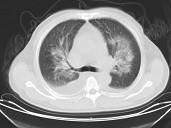

男,32岁,CT图像如图,最可能的诊断为 ( )A.肺水肿并双侧胸腔积液B.周围型肺癌C.肺动静脉瘘D.肺错构瘤E.炎性假瘤

问题 男,32岁,CT图像如图,最可能的诊断为 ( )

选项 A.肺水肿并双侧胸腔积液 B.周围型肺癌 C.肺动静脉瘘 D.肺错构瘤 E.炎性假瘤

答案 A